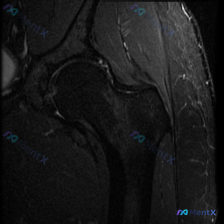

最近看到一张髋关节MRI冠状位T2加权像的病例资料,患者主要关注是否存在髋臼唇病变。先看一下图像的基本表现:股骨头形态完整,皮质光整,内部信号正常;关节间隙尚可,未见明显异常狭窄或增宽;髋臼外上方盂唇结构连续,未见明显撕裂导致的异常高信号裂隙或撕脱样改变;外侧大转子周围软组织可见局部高信号影(水肿)...